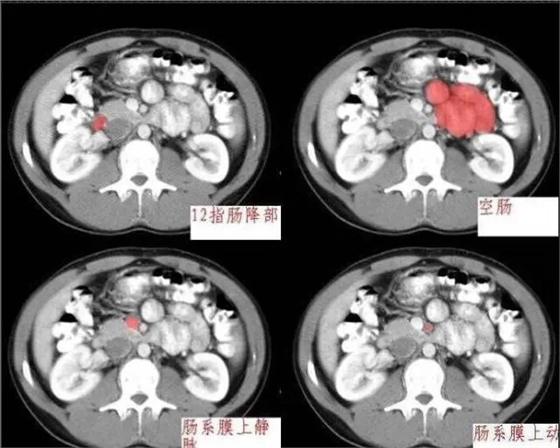

640.webp (2).jpg